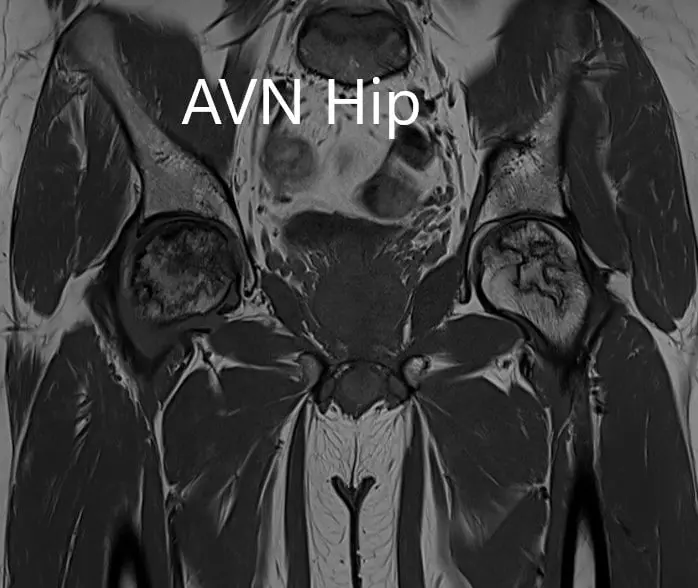

T1WI coronal section of MRI showing AVN hip.

Hypointense areas were present on both T1WI and T2WI on both the head of the femur suggestive of sclerosis. Surrounding bone marrow edema was present and the bilateral necrotic area was approximately 70%.